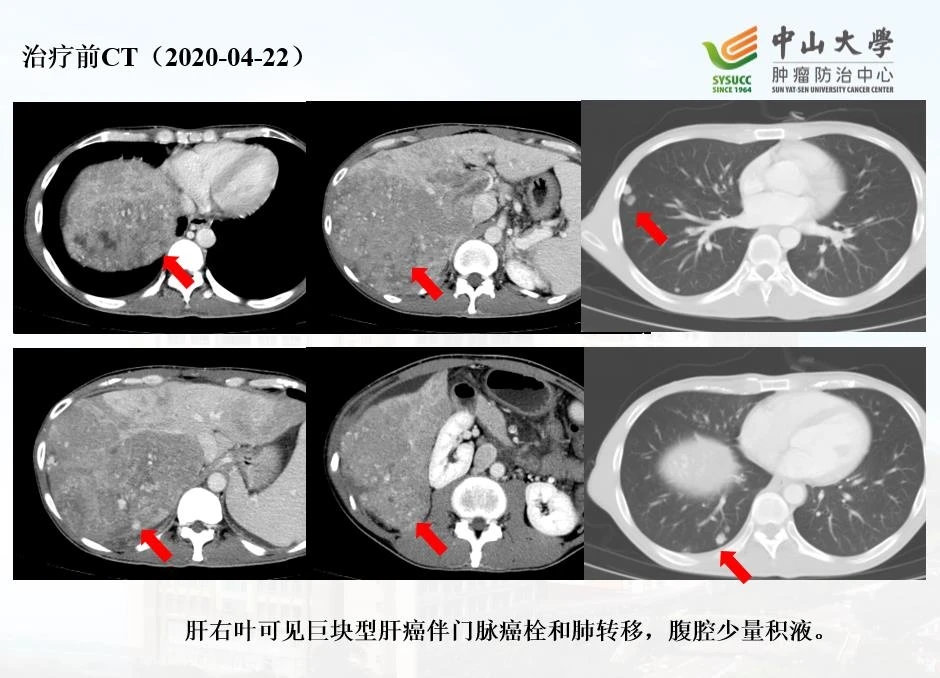

“一开始,右上腹部隐隐作痛,越来越重。”他立即到医院检查。在等候检查结果出炉的几天里,他的身体状况迅速恶化,腹胀、没胃口、乏力……面对“肝细胞肝癌C期(晚期),肝细胞肝癌伴门脉癌栓和肺转移,腹腔少量积液”的诊断报告,他不甘心,辗转找到范卫君教授求助。

以赵言为例:

HAIC PD-1抗体动脉灌注 靶向治疗,第一个疗程后复查CT见上图( 2020-05-12 ),肝内及肺内病灶较前明显缩小。